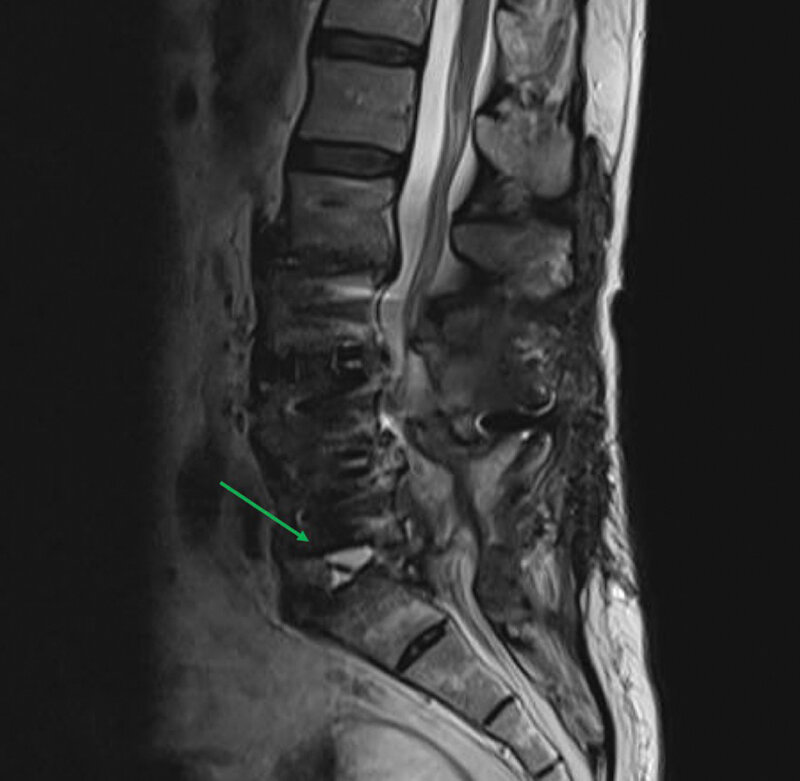

Na ressonância magnética, as sequências T2 e T2* têm objetivos diferentes. O T2 tradicional (Spin Echo ou FSE) destaca estruturas com alto teor de água, como o líquido cefalorraquidiano, edema e inflamações. Já o T2* (Gradient Echo ou SWI) é extremamente sensível a variações de campo magnético, como sangue, calcificações e metais.

- Uso comum: Edema cerebral, abcessos, tumores, lesões medulares.

- Vantagem: Alta qualidade de imagem e menos artefatos de suscetibilidade.